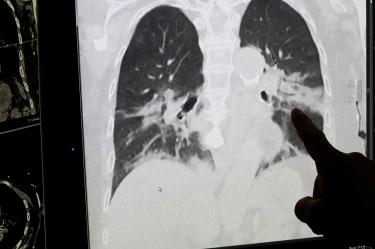

El director de la Organización Mundial de la Salud (OMS), Tedros Adhanom Ghebreyesus, advirtió que el nuevo coronavirus va a estar presente “durante mucho tiempo”, sigue siendo “extremadamente peligroso” y la “mayoría de la población” sigue siendo susceptible a infectarse.

En rueda de prensa dijo que las epidemias que ha provocado el nuevo coronavirus en muchos países pueden volver a resurgir “fácilmente”, por lo que pidió que no se asiente la “autocomplacencia”, porque todavía queda un “largo camino” que recorrer.

La mayoría de los países todavía están en las primeras etapas de sus epidemias, y algunos que se vieron afectados al comienzo de la pandemia ahora están comenzando a ver un resurgimiento en los casos. No se equivoquen, tenemos un largo camino por recorrer. Este virus estará con nosotros durante mucho tiempo”, aseveró el director general del organismo de la ONU